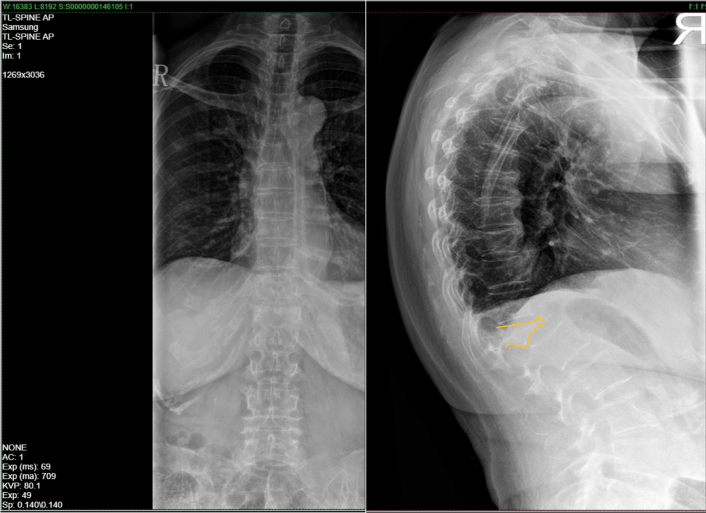

Spine X-ray upon admission

Spine X-ray showing wedge compression fracture of vertebrae